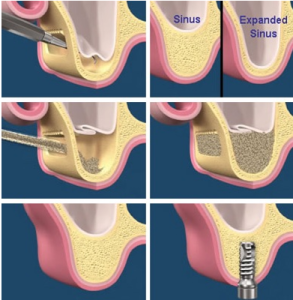

Sinus lift surgery can help correct this problem by raising the sinus floor and developing bone for the placement of dental implants. Several techniques can be used to raise the sinus and allow for new bone to form.

In one common technique, an incision is made to expose the bone. Then a small circle is cut into the bone. This bony piece is lifted into the sinus cavity, much like a trap door, and the space underneath is filled with bone graft material. Your periodontist can explain your options for graft materials, which can regenerate lost bone and tissue. Finally, the incision is closed and healing is allowed to take place. Depending on your individual needs, the bone usually will be allowed to develop for about four to 9 months before implants can be placed. After the implants are placed, an additional healing period is required. In some cases, the implant can be placed at the same time the sinus is augmented. Undergoing sinus lift surgery has been shown to greatly increase your chances for successful implants that can last for years to come. Many patients experience minimal discomfort during this procedure.

In the most common sinus augmentation technique, a tiny incision is made near the upper premolar or molar region to expose the jawbone. A small opening is cut into the bone and the membrane lining the sinus on the other side of the opening is gently pushed upward. The underlying space is filled with bone graft material and the incision is closed. The bone which is used for this procedure may be from your own body or from a cadaver. Sometimes the periodontist might use synthetic materials which can also stimulate bone formation. The implants are placed after healing has occurred; this will depend on the individual case. Sinus augmentation has been shown to increase the success of dental implant procedures.

Your surgeon will cut the gum tissue where your back teeth used to be. The tissue is raised, exposing the bone. A small, oval window is opened in the bone. The membrane lining the sinus on the other side of the window separates your sinus from your jaw. This membrane is gently pushed up and away from your jaw.

Granules of bone-graft material are then packed into the space where the sinus was. The amount of bone used will vary, but usually several millimeters of bone is added above the jaw.

Once the bone is in place, the tissue is closed with stitches. Your implants will be placed four to nine months later. This allows time for the grafted material to mesh with your bone. The amount of time depends on the amount of bone needed.